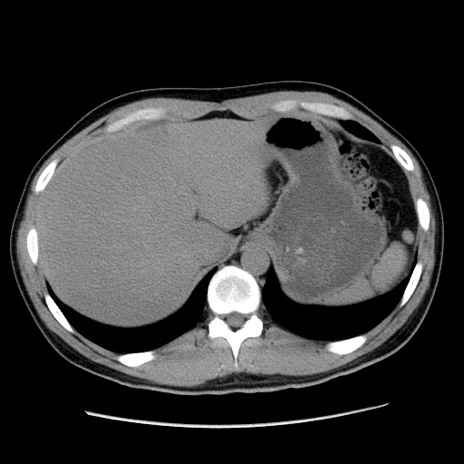

冠状断像

【症例】20歳代 男性

【主訴】心窩部痛

【現病歴】今朝より上腹部痛あり。一旦軽快していたが再度出現したため救急要請。昨日夕に白身の魚を含む刺身を食べた。

【身体所見】BP 136/89mmHg、HR 74/min、BT 37.0℃、腹部:膨満、軟、心窩部に圧痛あり。反跳痛なし、筋性防御なし、腸雑音やや亢進あり。

【データ】WBC 17700、CRP 0.48